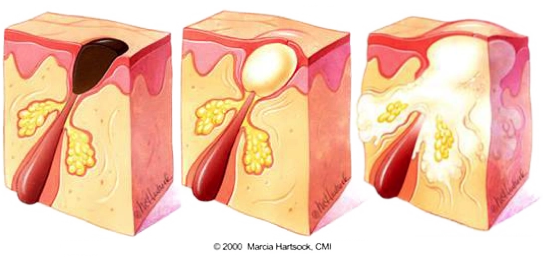

Comedones & Enlarged Pores

Open Comedones (Blackheads) The characteristic black hue of these comedones isn't a sign of embedded dirt or grime. Instead, it's the result of oxidation reactions when the trapped oil and skin cells are exposed to the air.

Closed Open (Whiteheads) are pores that are completely sealed with a thin layer of skin, unlike blackheads. This seal stops oxidation, causing small, light-colored bumps that may feel slightly raised.

Papules & Pustules

Papules are small red, solid, and inflamed bumps on the skin that do not contain pus.

Pustules are infected papules that have accumulated pus, white or yellow, from bacterial activity.

Both are a result of from pores becoming clogged with oil and dead skin cells.